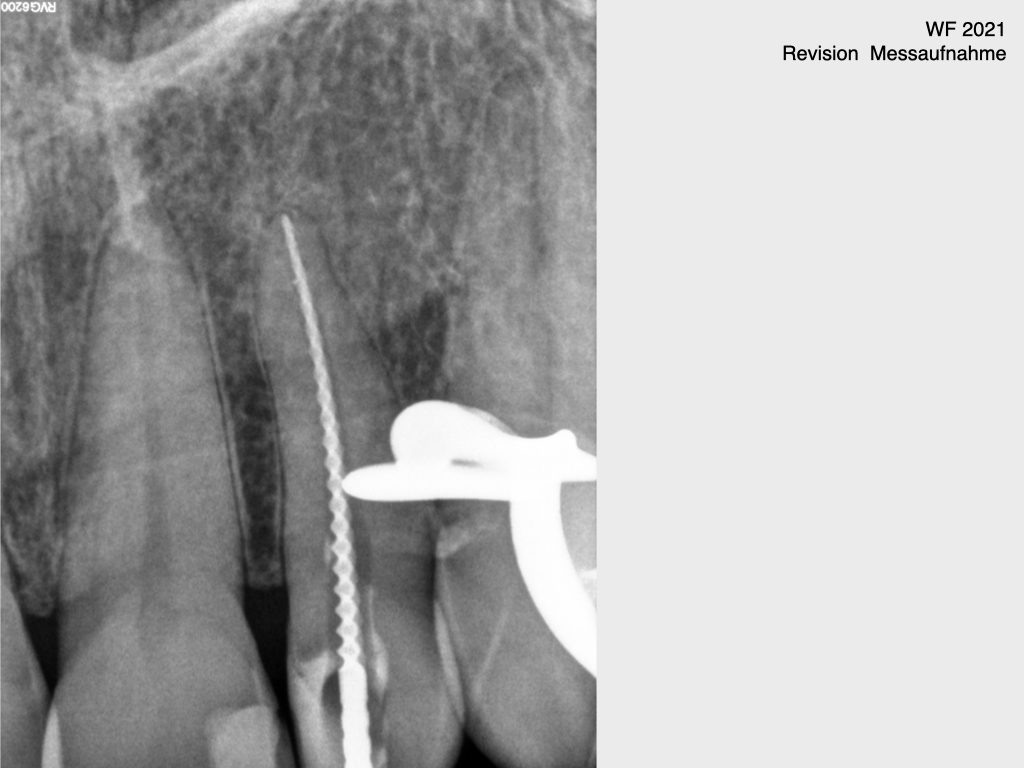

Frontzahn 22 (3)